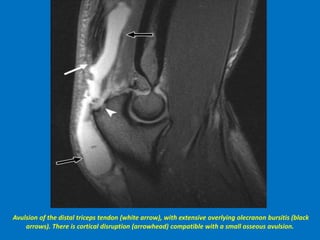

Avulsion of the distal triceps tendon (white arrow), with extensive overlying olecranon bursitis (black

arrows). There is cortical disruption (arrowhead) compatible with a small osseous avulsion.